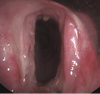

Tráquea y bronquios principales

Estenosis traqueal post traqueotomía

Estenosis traqueal post intubación

Granulomas traqueales post traqueotomía

Infiltración traqueal por Ca epidermoide pulmonar

Neoplasia de carina principal